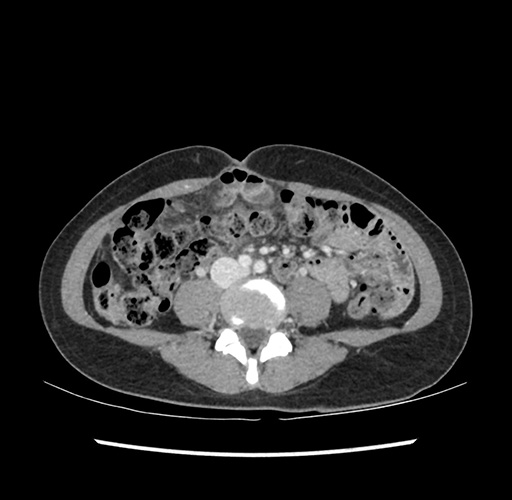

Imaging Analysis

Look through the patient's CT scan to identify any areas of concern for the necessary procedure.

Based on your CT findings, which issue(s) would give reason for "planned slowing down moment(s)" in this case?